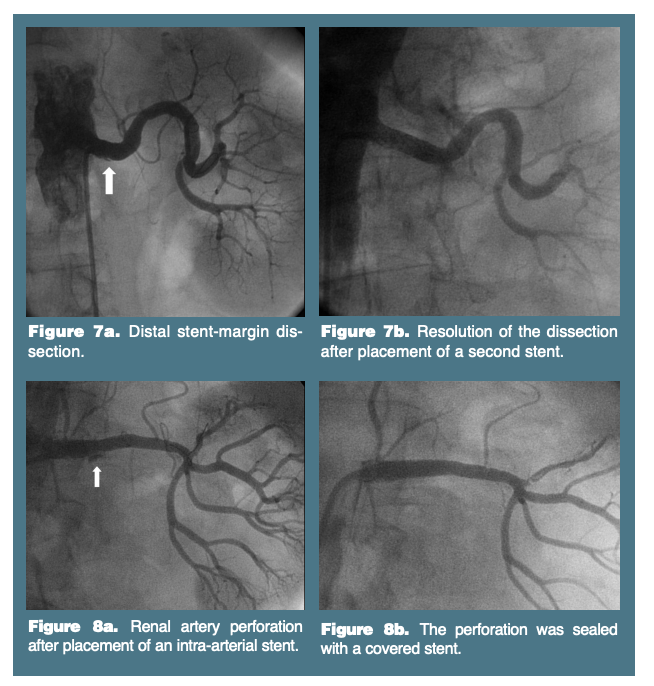

The majority of complications associated with percutaneous renal artery revascularization are related to arterial access, including hematoma, retroperitoneal hemorrhage, pseudoaneurysm, arterio-venous fistula and infection. Renal artery spasm (Figure 4) and wire-straightening pseudo-lesions are not uncommon occurrences and should be recognized and treated appropriately. Spasm responds to vasodilators, and pseudo-lesions will resolve when the wire is retracted, allowing a tortuous artery to assume its normal shape. Renal artery dissection is treated with intra-arterial stent placement (Figure 7). Distal wire perforation may resolve spontaneously with reversal of anticoagulation or require coil embolization. Renal artery perforation may respond to prolonged balloon inflation with reversal anticoagulation, or may require the placement of an intra-arterial stent graft (Figure 8). However, if these techniques are unsuccessful, emergent nephrectomy or aorto-renal bypass may be necessary. Atheroembolization to the kidneys, bowel or lower extremities may result in renal failure, ischemic bowel or digital ischemia, respectively.